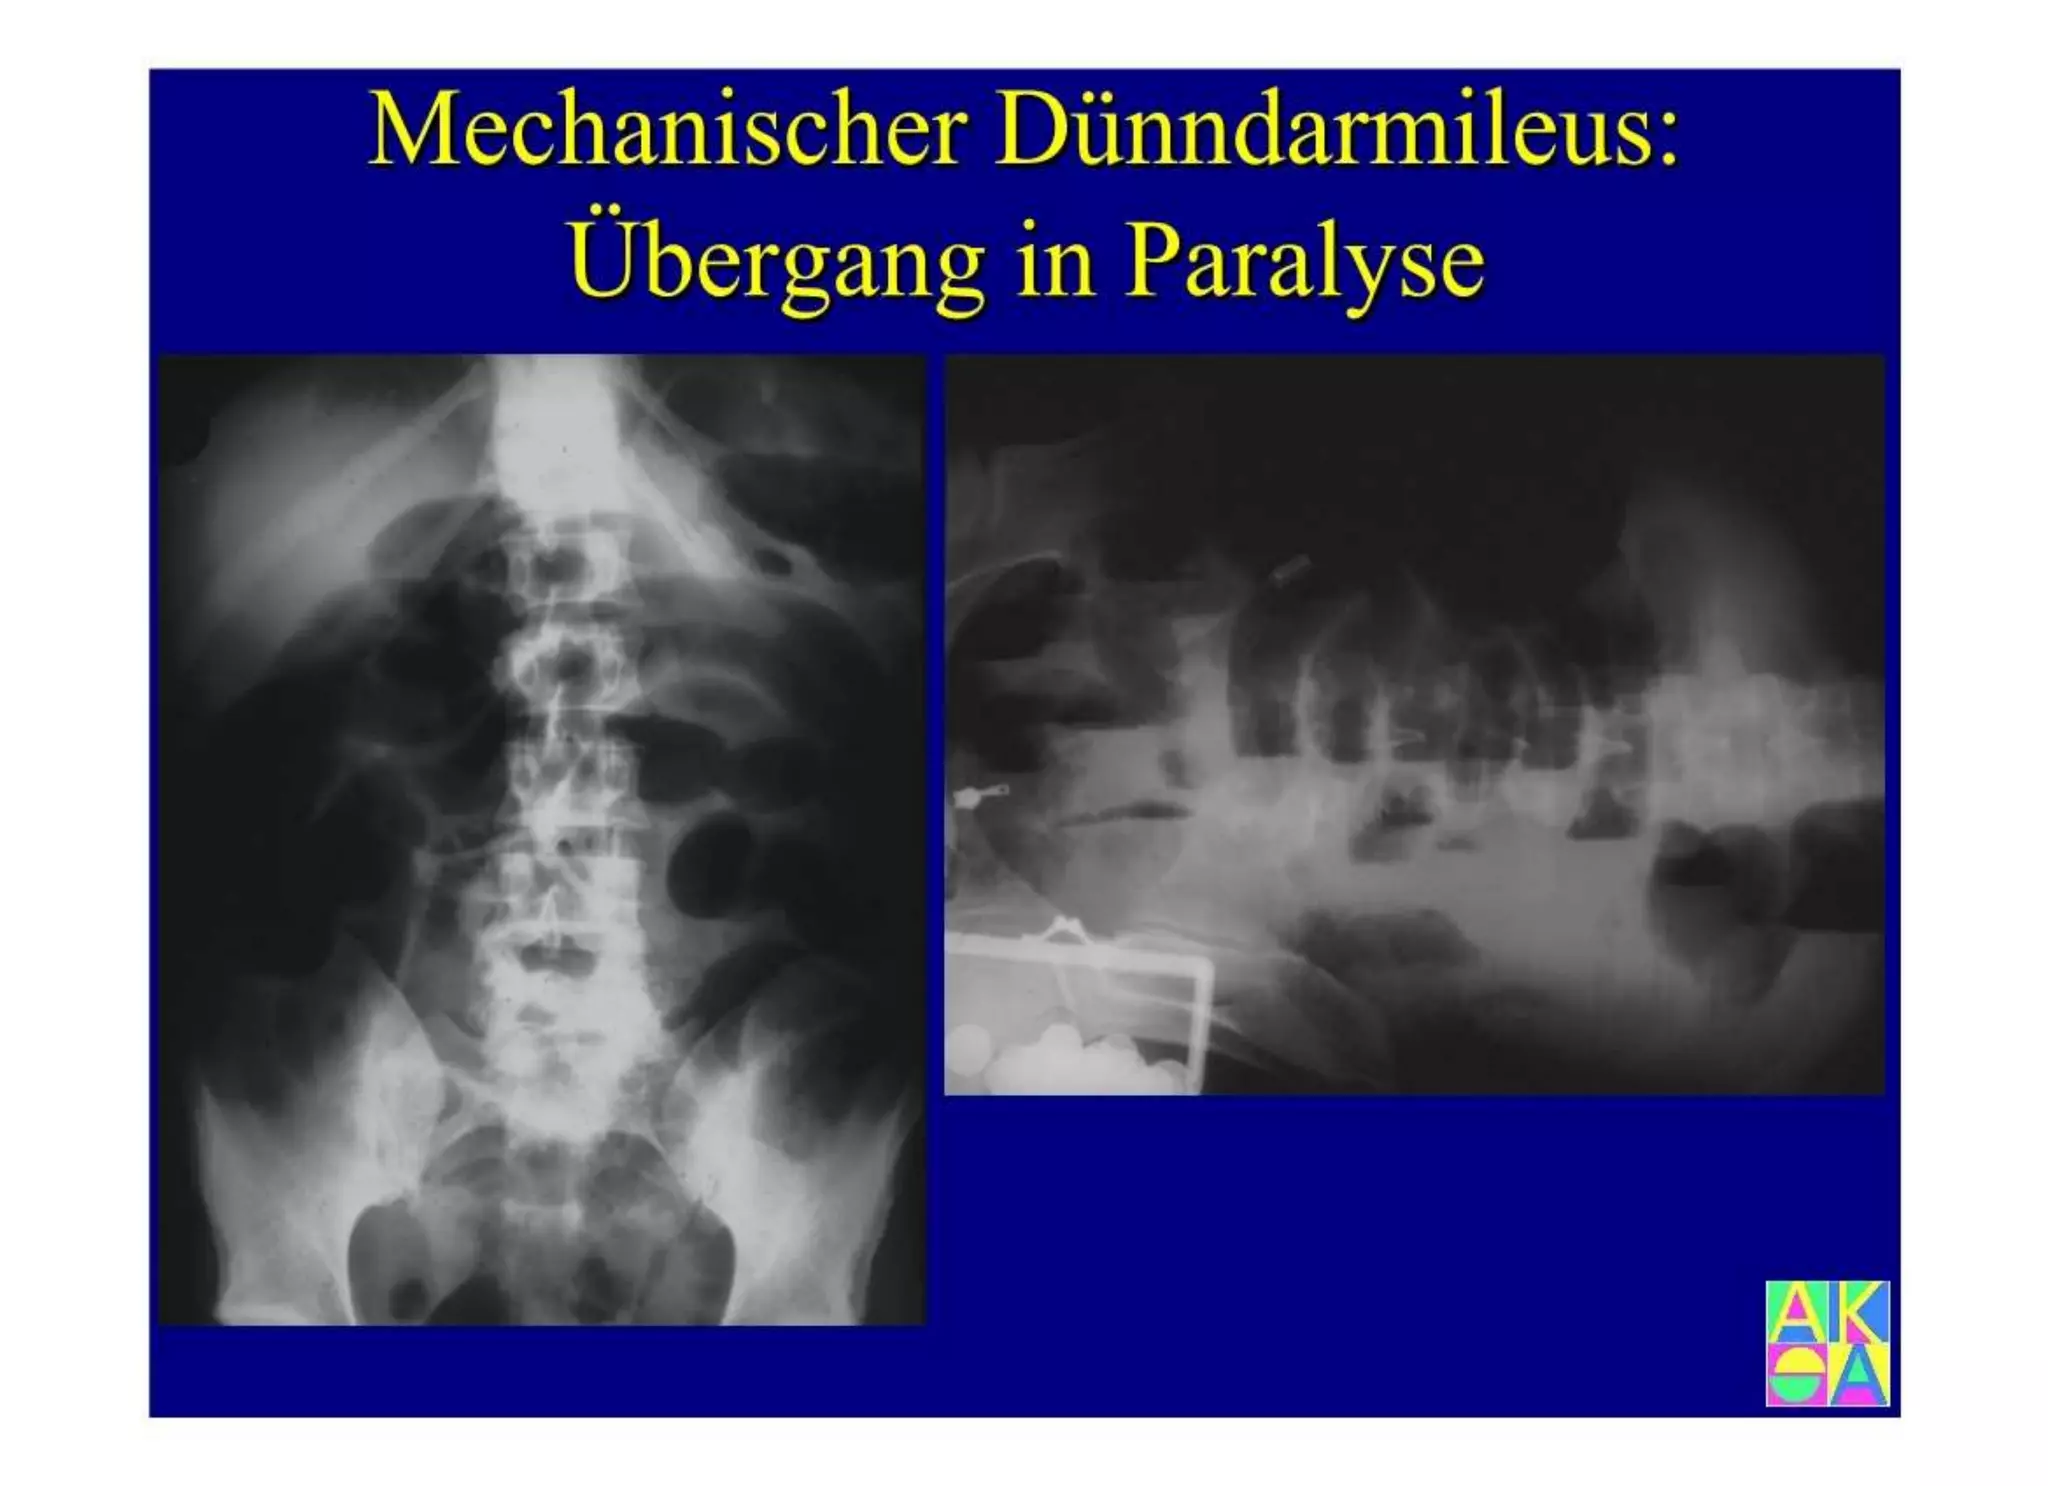

Chronische Enteropathie und Ileus, Dünndarm und Dickdarmdiagnostik, Mechanischer und paralytischer Ileus, Eingeklemmte Darmabschnitte, aufgereihter Bridenileus, und dazu Dickdarmileus, eingeklemmte Hernien, Weitergabeskript